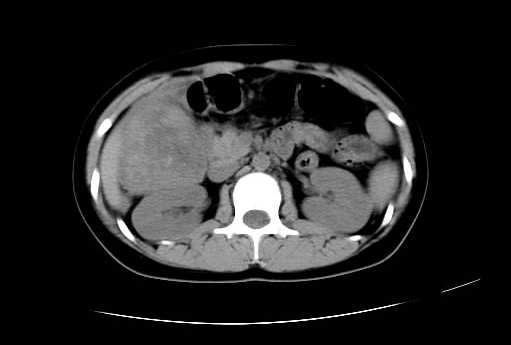

女 16岁  右上腹痛一天,无其他不适

肿块最大径位于十二指肠降段与水平段移行处,并且与肝脏压迹呈“0”形征,可以考虑位于肝外并与胃肠道关系紧密,考虑胃肠道间质瘤(gist)可能较大,须除外神经节起源肿瘤。

肿块与十二指肠关系密切,支持间质瘤诊断.肝脏与结肠均为受压改变.

右下腹巨大肿快,密度不均匀,内见坏死低密度区,边界清楚,与周边胀器明显有分界,未见强化,多考虑来源于间叶组织的良性肿物.

病灶巨大,少部分向肠腔内生长,大部分向长腔外生长。其密度不均匀,增强显示明显不均匀强化,并见有大片状始终不强化的不规则坏死液化区。虽然病灶中上部形态尚可,病人又如此年轻,但中下部形态、密度、强化特点强烈提示为恶性病灶。综上,我考虑本病例为:恶性胃肠道间质瘤。